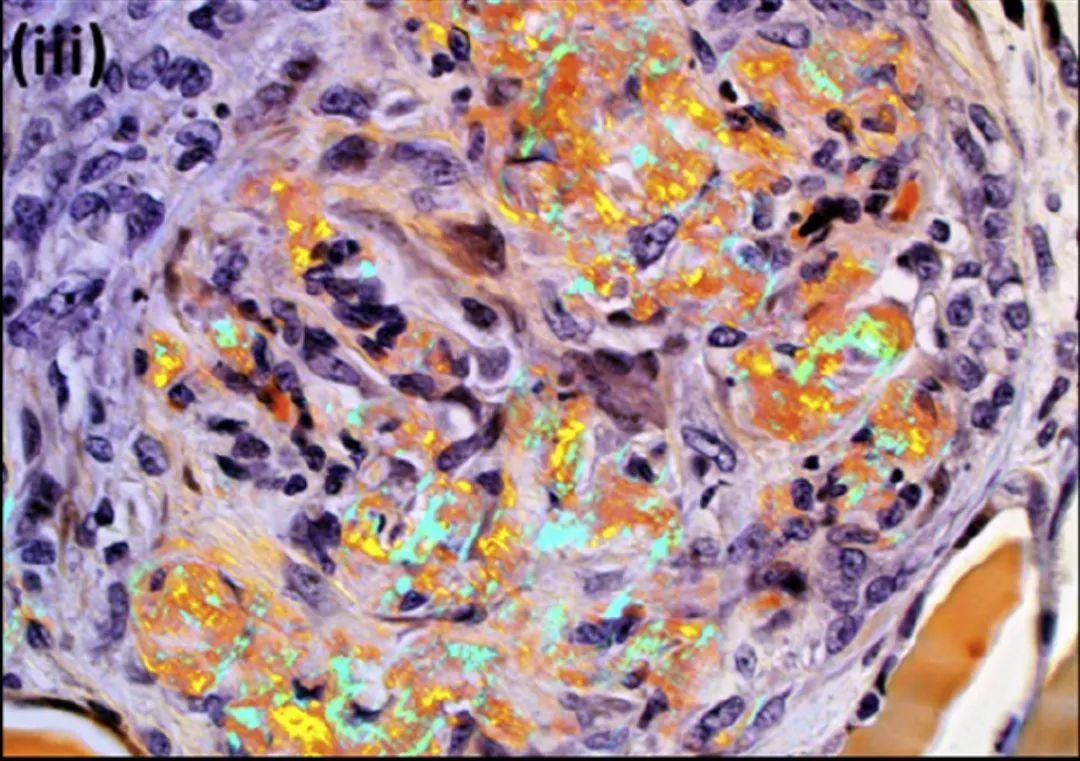

48 个肾小球,1 个全球硬化,60%-70% 肾小球有细胞性新月体,部分肾小球有基底膜破裂伴纤维蛋白渗出(图i和ii,箭头所示)。少数肾小球 (<5%) 显示纤维细胞性新月体。所有肾小球均表现出节段性至全球性系膜区均质性增宽。刚果红染色证实为淀粉样物质,偏振光下呈苹果绿双折射(图iii)。免疫组化显示血清淀粉样蛋白 A 呈阳性 (图iv)。部分毛细血管袢有节段性毛细血管内细胞过多,主要为单核白细胞和少量中性粒细胞。小动脉和间质(主要在髓质中)中也可见淀粉样物质沉积。没有动脉炎,有轻度间质纤维化